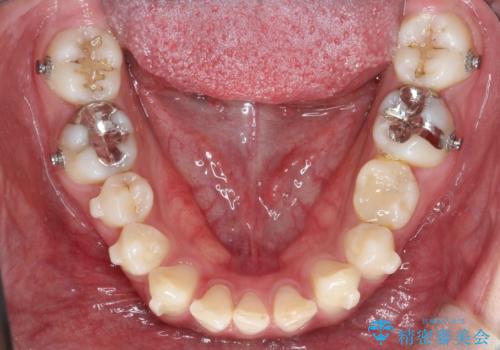

【インビザライン】空隙歯列の矯正

- 前歯の隙間を主訴に来院されました。

なるべく目立たない治療を希望されましたので、インビザラインにて治療を行なっております。

単純に前歯の隙間の閉鎖をしてしまうと、前歯に早期接触が生まれ、臼歯が噛まなくなってしまいます。適切な治療計画を立てることで、噛み合わせも良好な結果を得ることができました。